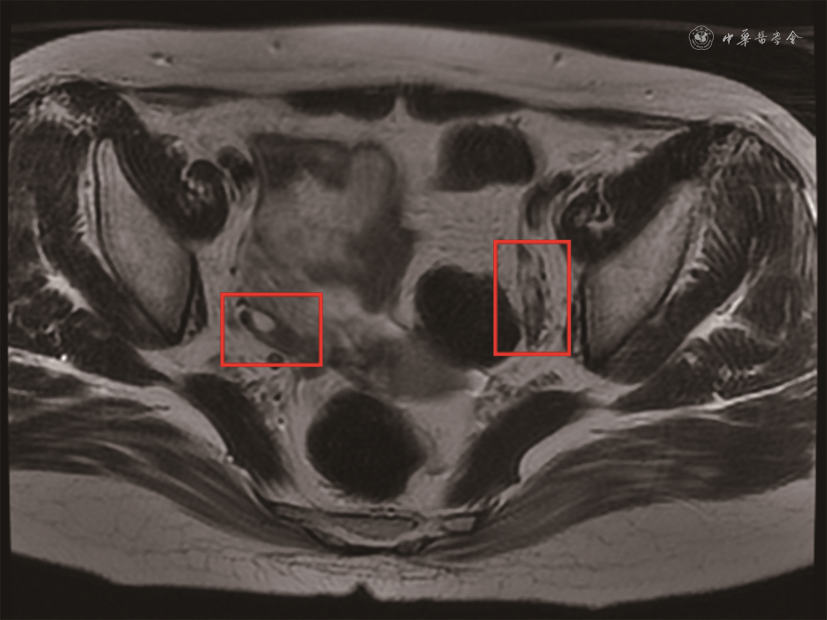

入院体检:血压 106/70 mmHg(1 mmHg=0.133 kPa),脉搏94次/min,呼吸20次/min,心率94次/min;心、肺未见明显异常,对答切题,言语稍慢,右侧鼻唇沟稍浅,示齿口角稍偏左,右上肢近端肌力Ⅴ-级,远端肌力Ⅳ级,腱反射较对侧活跃,右手除拇指外4指掌侧针刺觉减退,右上肢指鼻欠稳准。入院后查血常规,白细胞3.81×109/L,血红蛋白132 g/L,血小板193×109/L;尿常规,尿蛋白、尿潜血(-),24 h尿蛋白0.13 g;肝肾功能,白蛋白43 g/L,肌酐43 μmol/L,尿酸278 μmol/L;总胆固醇3.08 mmol/L,甘油三酯0.66 mmol/L,低密度脂蛋白胆固醇1.15 mmol/L;凝血酶原时间12.1 s(参考值10.4~12.6 s),活化部分凝血酶原时间26.8 s(参考值23.3~32.5 s),国际标准化比值1.05(参考值0.86~1.14),纤维蛋白原2.85 g/L(1.80~3.50 g/L),D-二聚体0.15 mg/L FEU(参考值0~0.55 mg/L FEU);同型半胱氨酸15.1 μmol/L(参考值<15.0 μmol/L),叶酸5.1 μg/L(参考值>4.0 μg/L),维生素B12 246 ng/L(参考值180~914 ng/L);易栓症筛查,蛋白C 119%(参考值70%~140%),蛋白S 62%(参考值76%~135%),活化蛋白C抵抗比值为2.9(参考值>2.1),抗凝血酶Ⅲ 116%(参考值83%~128%);性激素,LH 60.21 IU/L(绝经期10.87~58.64 IU/L),FSH 79.84 IU/L(绝经期>40.00 IU/L),雌二醇34 ng/L(绝经期<40 ng/L),孕激素0.24 μg/L(绝经期<0.78 μg/L),睾酮<0.1 μg/L(0.10~0.75 μg/L);红细胞沉降率(ESR)24 mm/1h,IgG 20.66 g/L,超敏C反应蛋白(CRP)0.28 mg/L;补体C3 1.125 g/L,补体C4 0.116 g/L;抗核抗体 1∶640(均质型),抗双链DNA抗体(ELISA)169 IU/ml,抗Sm抗体阴性,抗SSA抗体强阳性(免疫印迹法90),抗心磷脂抗体(ACL)-IgG阳性 94.9~95.2 GPLU/ml(参考值<8.0 GPLU/ml),抗β2糖蛋白Ⅰ(β2GPⅠ)抗体-IgG阳性 38.2~39.9 AU/ml(参考值<16.0 AU/ml),狼疮抗凝物(LA)阴性,抗中性粒细胞胞质抗体阴性。子宫双附件超声检查(经腹):子宫、双卵巢体积稍小。经颅多普勒发泡试验示,双侧大脑中动脉可见约4个微栓子信号;头颅MRA及磁共振静脉造影(MRV)未见明显异常。综合患者临床表现及自身抗体检查结果,符合系统性红斑狼疮(SLE)、抗磷脂综合征(APS)诊断,合并急性卒中,立即停用性激素替代治疗,加强脑血管病二级预防治疗,予阿司匹林(100 mg,1次/d,口服)、阿托伐他汀(20 mg,1次/d,口服)治疗;针对SLE、APS,予泼尼松(60 mg,1次/d,口服)、吗替麦考酚酯(0.75 g,2次/d,口服)、羟氯喹(0.2 g,2次/d,口服)治疗。此后患者神经系统症状恢复正常,言语流利。泼尼松规律减量(每周减量5%),期间未使用性激素替代治疗。2019年12月北京协和医院门诊查卵巢MRI示,子宫、双侧卵巢形态小,右卵巢可见一小卵泡影(图1)。2020年1月10日泼尼松减至10 mg、1次/d时患者月经来潮,复查LH 6.06 IU/L(卵泡期2.40~12.60 IU/L),FSH 11.01 IU/L(卵泡期3.50~12.50 IU/L),雌二醇31.9 ng/L(卵泡期12.4~233.0 ng/L),孕酮0.218 μg/L(卵泡期 0.057~0.894 μg/L)。此后规律行经至今,行经天数3~4 d,月经周期28 d,经量正常。

放射科医师 目前有研究认为,自身免疫性卵巢炎是由于原始卵泡的异常发育,导致窦状卵泡无法形成,而被黄体化的、体积较大囊泡取代所致,因此自身免疫性卵巢炎早期可以见到卵巢内较大的囊状结构[14]。本例患者闭经初期超声检查发现双侧卵巢无窦状卵泡,左侧卵巢存在较大的囊泡,卵巢及子宫体积均较小,符合自身免疫性卵巢炎的早期表现。此外,卵巢炎症性改变可通过卵巢MRI辨别,但患者行卵巢MRI时已为足量糖皮质激素及免疫抑制剂治疗后,未见明确炎症表现,但仍可见双侧卵巢体积较小,可能为卵巢损伤后改变。经糖皮质激素和免疫抑制剂治疗后,患者卵巢MRI示一小卵泡影,数日后患者即恢复月经来潮,提示糖皮质激素、免疫抑制剂治疗有效。

风湿免疫科医师 自身免疫性卵巢炎诊断的金标准为卵巢病理切片发现淋巴细胞浸润,但由于患者新发卒中,规律应用抗栓治疗,存在有创操作病理活检的相对禁忌,因此未能获得病理诊断。有文献报道,部分患者亦可通过筛查自身免疫性卵巢炎相关自身抗体证实自身免疫性卵巢炎的诊断[10],相关自身抗体主要包括针对透明带、颗粒细胞、泡膜细胞、黄体素及性激素合成酶的抗体[7,12,15],受国内自身抗体检测条件所限,本例患者未行相关检测。然而患者自身免疫病SLE诊断明确,超声及卵巢MRI显示双侧卵巢形态小,闭经前未使用影响卵巢功能的药物,闭经后不久即出现明确的SLE疾病活动,且大剂量泼尼松、吗替麦考酚酯治疗后性激素水平及月经周期恢复正常,卵巢MRI检测到卵巢上有小卵泡影,以上均可支持SLE继发自身免疫性卵巢炎的诊断。目前尚无自身免疫性卵巢炎明确有效的治疗方案,临床主要应用的仍然是性激素替代治疗[10],但本例患者对症治疗后无诱导排卵,而针对原发病的糖皮质激素、免疫抑制剂治疗提示有效,这为自身免疫病合并自身免疫性卵巢炎的治疗提供了一种新的理念。本例提示,对无明确诱因突发卵巢功能减退者需积极筛查病因,条件允许可查卵巢MRI或自身免疫性卵巢炎相关自身抗体,以确定是否为自身免疫性卵巢炎,追问皮疹、关节痛、口腔溃疡等自身免疫病相关表现,必要时完善自身抗体筛查及系统评估,警惕自身免疫病继发自身免疫性卵巢炎可能,如明确原发病为SLE,需全面评估原发病活动水平,警惕SLE活动继发的自身免疫性卵巢炎可能,条件允许可考虑尝试大剂量糖皮质激素及免疫抑制剂治疗原发病,密切观察卵巢功能变化。